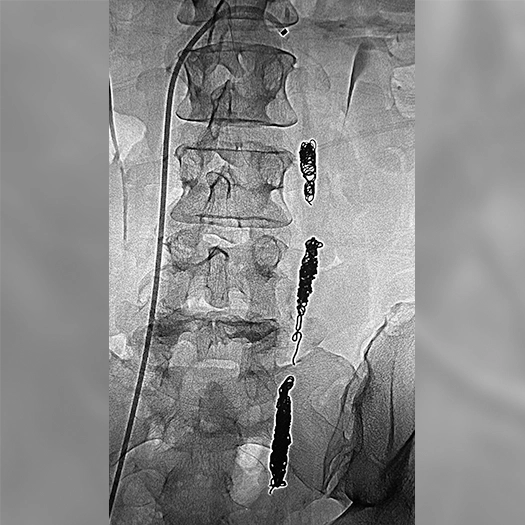

Ruby® XL Dr. Brandon Perry AdventHealth Orlando, FL

Zoomed in view of Ruby XL Detail

Coils Used: 8mm x 70cm POD XL and 70cm Packing Coil XL (bottom), 70cm Packing Coil XL (middle), 10mm x 35cm Ruby Standard and 12mm x 30cm Concerto (top)

Catheter: 80cm 5.5F Fogerty balloon w/ Cook 6 x 45cm Ansel-2 sheath